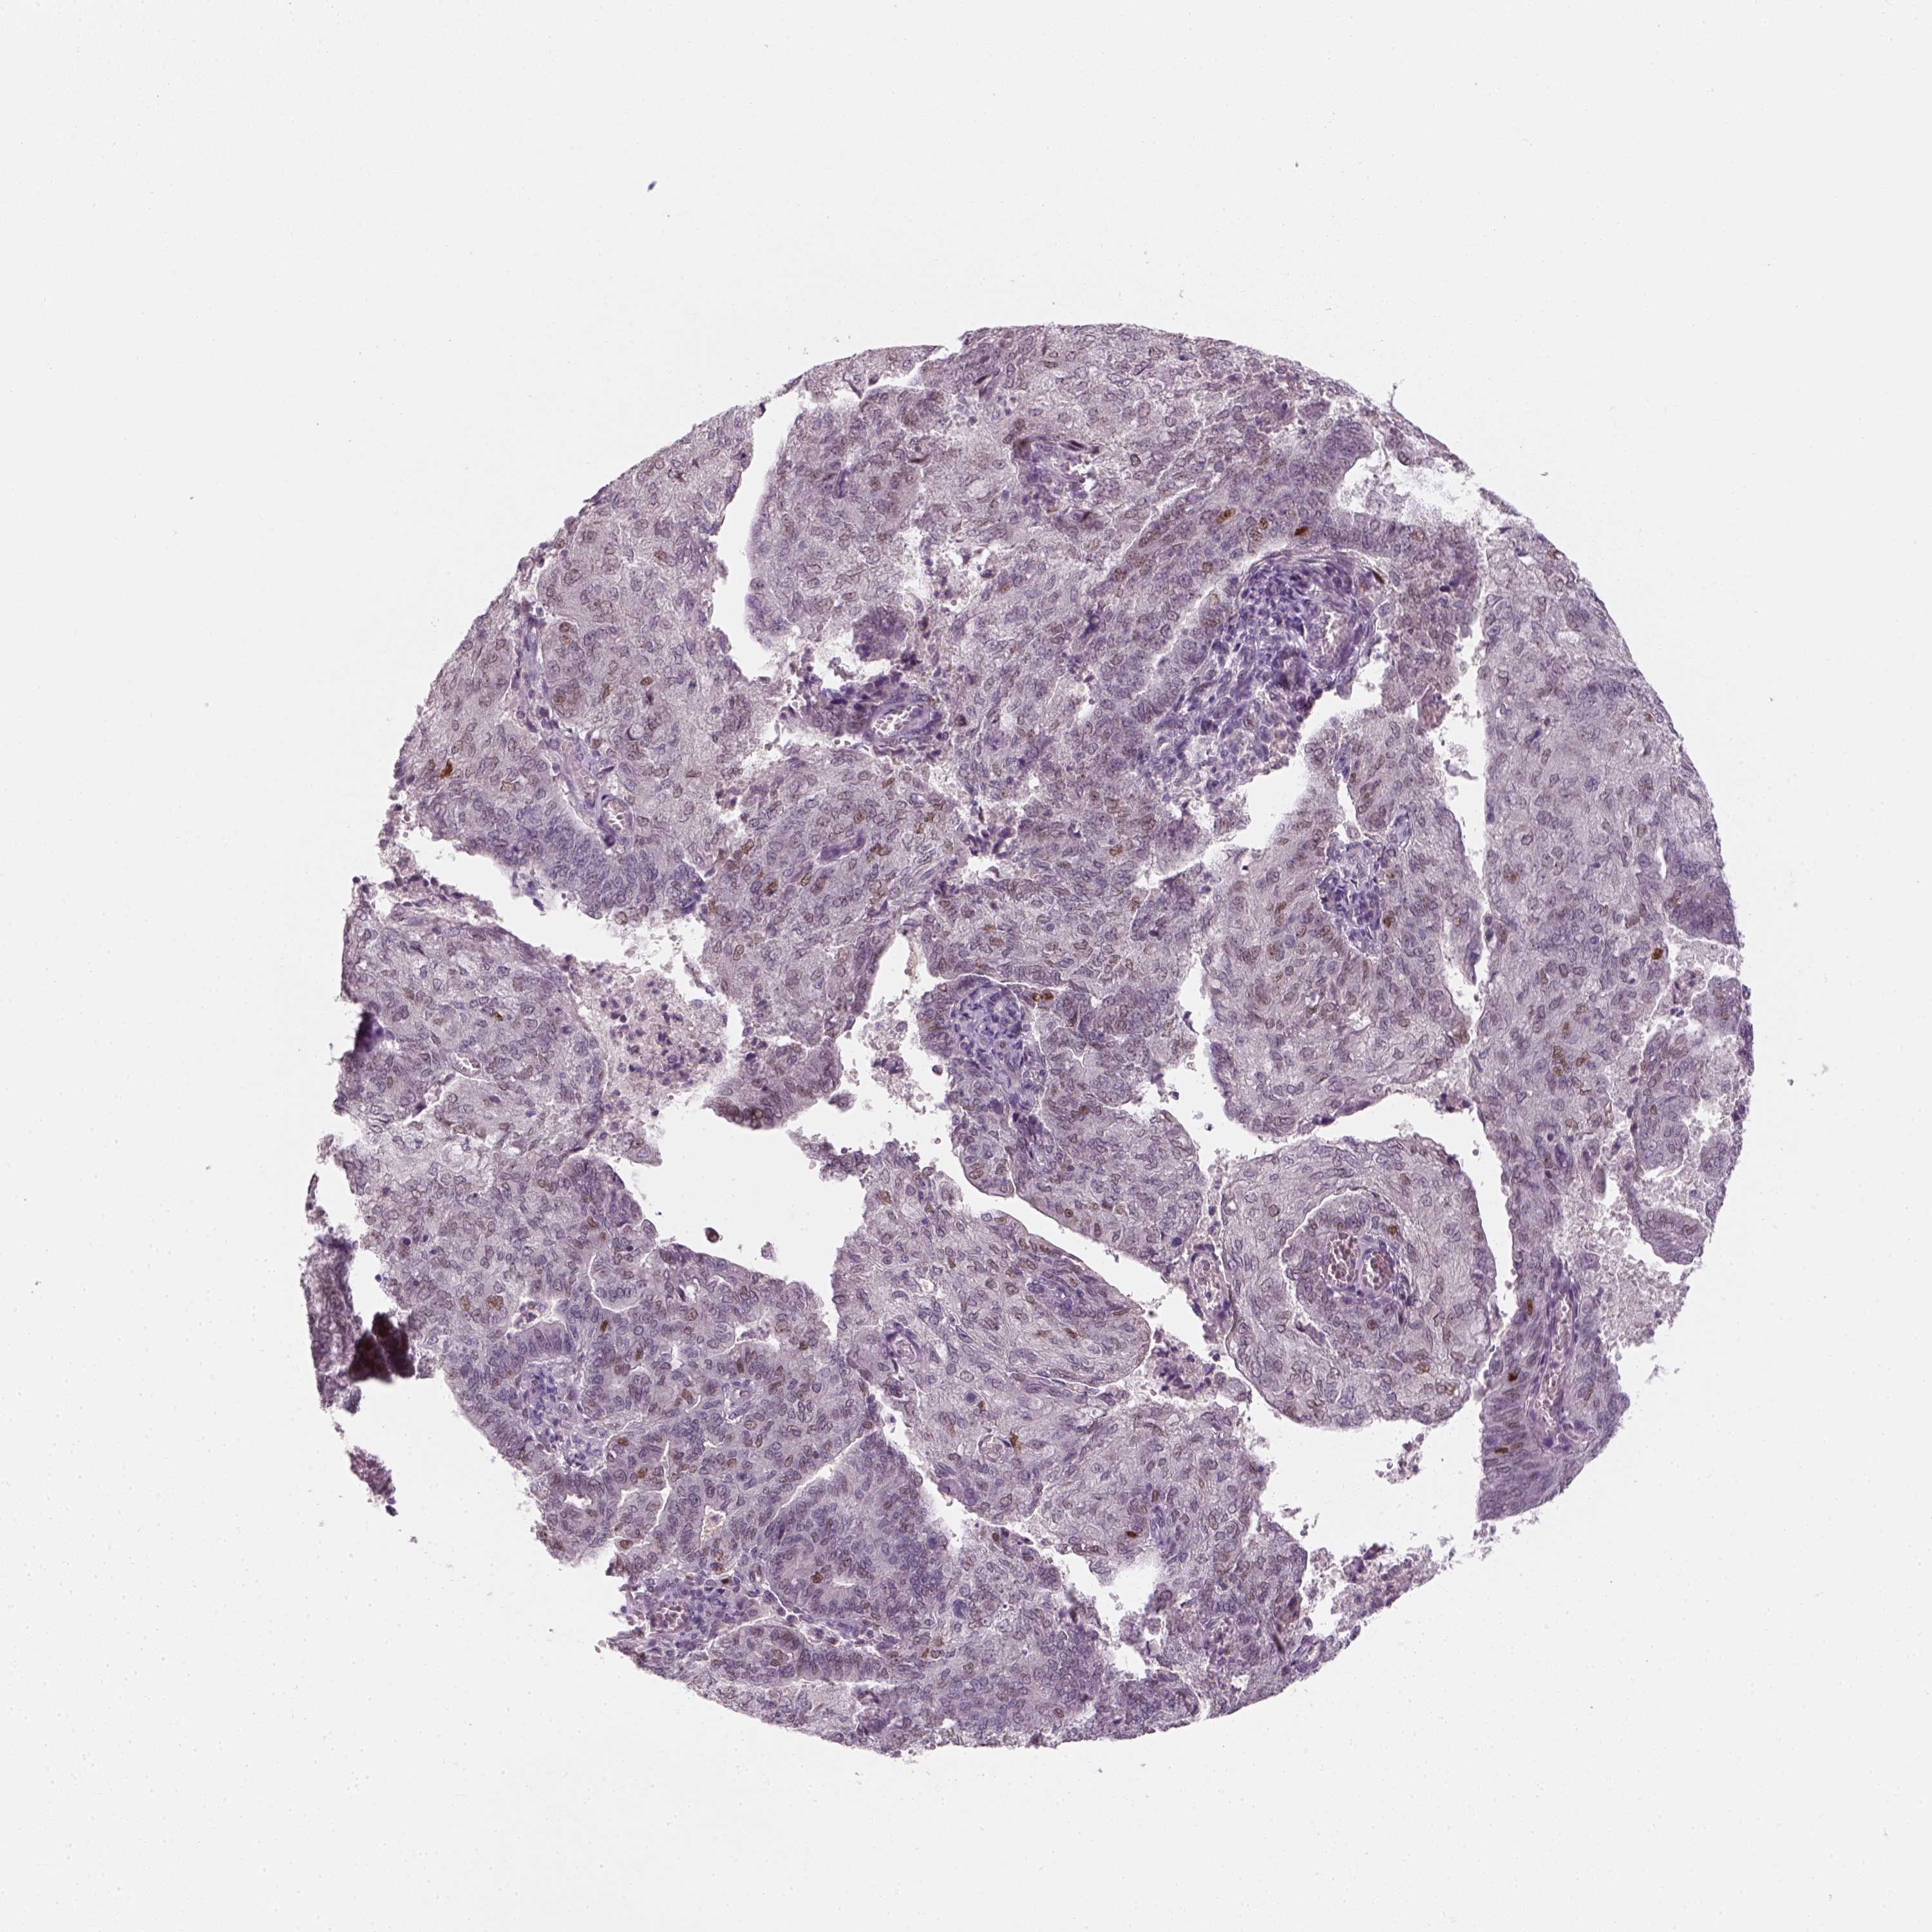

ENDOMETRIAL CANCER - Protein expressioni

A mouse-over function shows sample information and annotation data. Click on an image to view it in a full screen mode. Samples can be filtered based on level of antibody staining by selecting one or several of the following categories: high, medium, low and not detected. The assay and annotation is described here.

Note that samples used for immunohistochemistry by the Human Protein Atlas do not correspond to samples in the TCGA dataset.

Antibody stainingi

Antibody staining in the annotated cell types in the current human tissue is reported as not detected, low, medium, or high, based on conventional immunohistochemistry profiling in selected tissues. This score is based on the combination of the staining intensity and fraction of stained cells.

Each image is clickable and will lead to virtual microscopy that enables deeper exploration of all samples and also displays staining intensity scores, fraction scores and subcellular localization as well as patient and tissue information for each sample.

Antibody CAB002973

Antibody CAB039238

Antibody CAB039239

Antibody CAB072876

Staining

High

Medium

Low

Not detected

Intensity

Strong

Moderate

Weak

Negative

Quantity

>75%

75%-25%

<25%

None

Location

Nuclear

Cytoplasmic/membranous

Cytoplasmic/membranous,nuclear

Adenocarcinoma, NOS

Neoplasm, malignant, NOS

Adenocarcinoma, metastatic, NOS